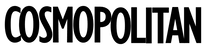

Discover your skin's genetic blueprint. Learn how your DNA influences skin issues, stress, and metabolism, so you can make evidence‑based care decisions.